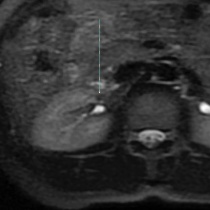

횡단면 fat-suppression 영상에서 크기가 작고, 신호강도가 강하게 fat-suppressed된 저신호강도의 병변이 초음파영상에서 결절이 확인된 부위와 일치한 곳에서 보입니다. 결절 내부에 지방이 풍부하게 포함되있다는 것을 의미하므로, renal cell carcinoma가 아닌 양성 angiomyolipoma 로 진단할 수 있는 사례입니다.

위 영상에서 보이듯이 감별진단과 내부 성분조성을 확인하는 데는 자기공명영상(MRI)이 유리하지만, 해상도가 떨어지므로 크기가 작은 결절의 발견과 모양을 확인하는데는 초음파영상이 훨씬 중요한 역할을 합니다.